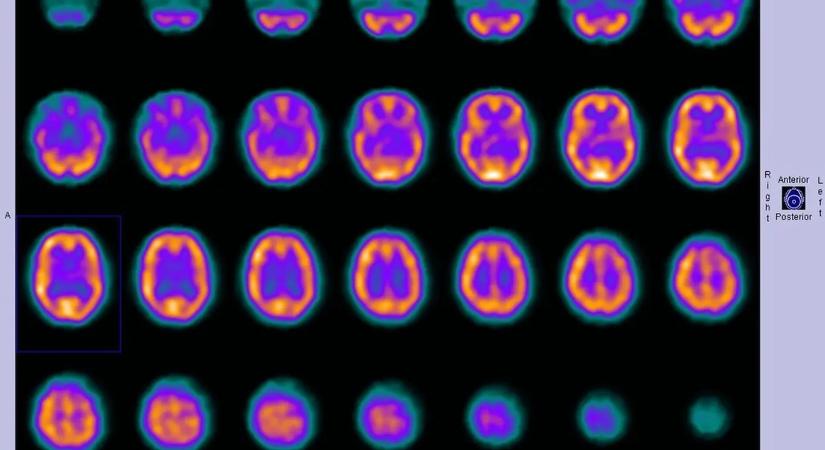

A legtöbben a halált egyfajta hirtelen csendként, sötétségként, vagy esetlegesen végleges lezárásként képzelik el. A tudomány viszont épp az ellenkezőjét mutatja, hogy az élet utolsó pillanatai jóval összetettebbek lehetnek. Úgy tűnik, az agy nem kapcsol ki azonnal , sőt, az utolsó másodpercekben akár olyan aktivitást is mutathat, amely az álmokhoz, az emlékezéshez vagy egy nagyon […] A A tudósok felfedezték, mit lát az ember a halál pillanatában bejegyzés először ÉrdekesMagazin.hu-én jelent meg.